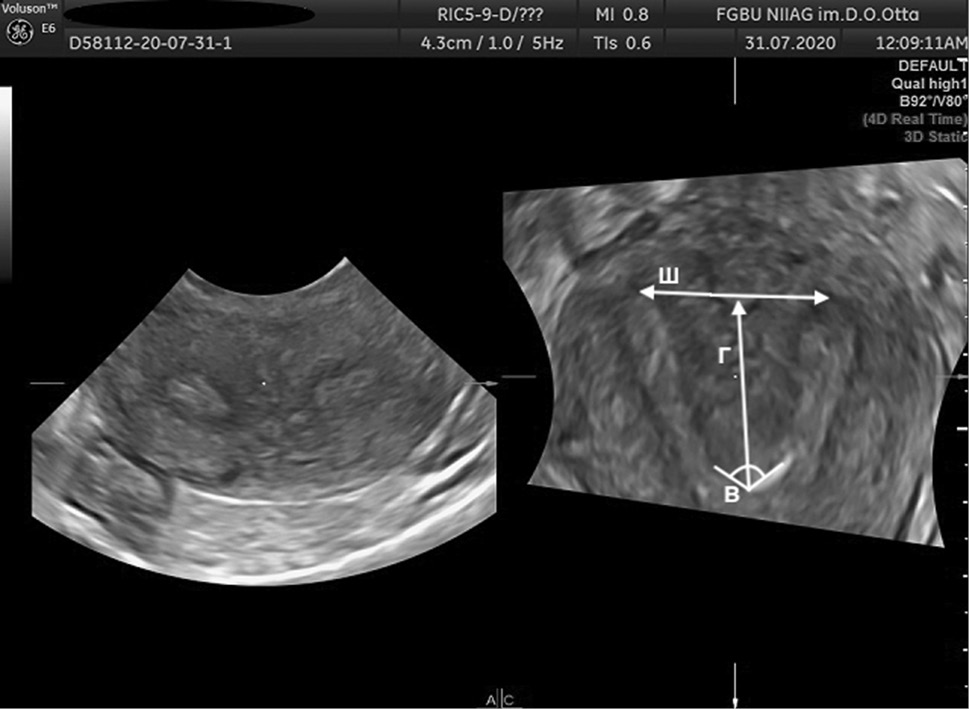

The AFS proposed to assess parameters, such as Г, cavity indentation; Ш, uterine cavity width; and B, angle of cavity indentation (Figs. 1–4).

Fig. 2. 3D ultrasound reconstruction of the uterine cavity: arcuate uterus, where Ш, uterine cavity width; Г, cavity indentation; B, angle of cavity indentation (120°)

Рис. 2. Ультразвуковая 3D-реконструкция полости матки — седловидная матка: Ш — ширина полости матки; Г — глубина вдавления полости матки; угол В — угол вдавления полости (120°)

Uterine septum is diagnosed using the following indicators: Г ≥15 mm, angle B <90º, while uterus arcuate is diagnosed using the following indicators: D ≥10 mm, but <15 mm and angle B >90° [11].